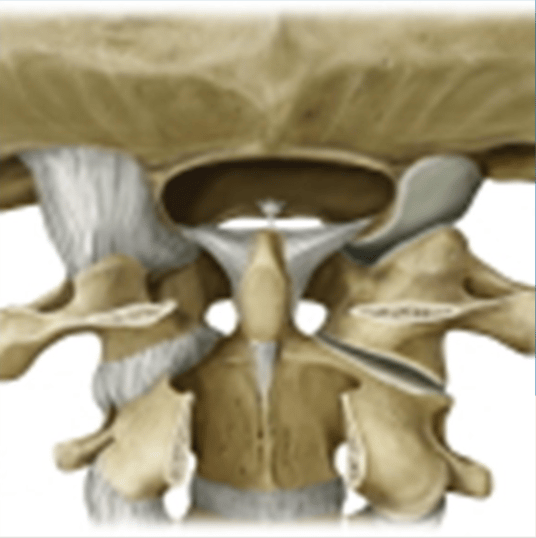

The C1 and C2 vertebrae contain numerous ligaments such as the alar and transverse ligaments that are easily damaged or torn during car crashes, even at relatively low speeds.

Damage to these ligaments results in symptoms such as headaches, neck pain, blurred vision, double vision, nausea, difficulty sleeping, and numerous other symptoms.

The DMX allows these injuries to be clearly visualized by both an adjustor, defense counsel, and jury alike. It is very obvious to watch one bone literally slide off of another as someone flexes their head side to side.

Because of its importance with balance and movement, damage to the upper cervical ligaments can be even more devastating.

Once the ligament damage has been identified with the DMX, appropriate specialist referrals may need to occur. In cases of sever upper cervical instability fusion surgery may even be a consideration.

There are very few neurosurgeons in the United States who perform C1-C2 fusions, so these referrals should be chosen carefully to ensure the best possible second opinion has been solicited.